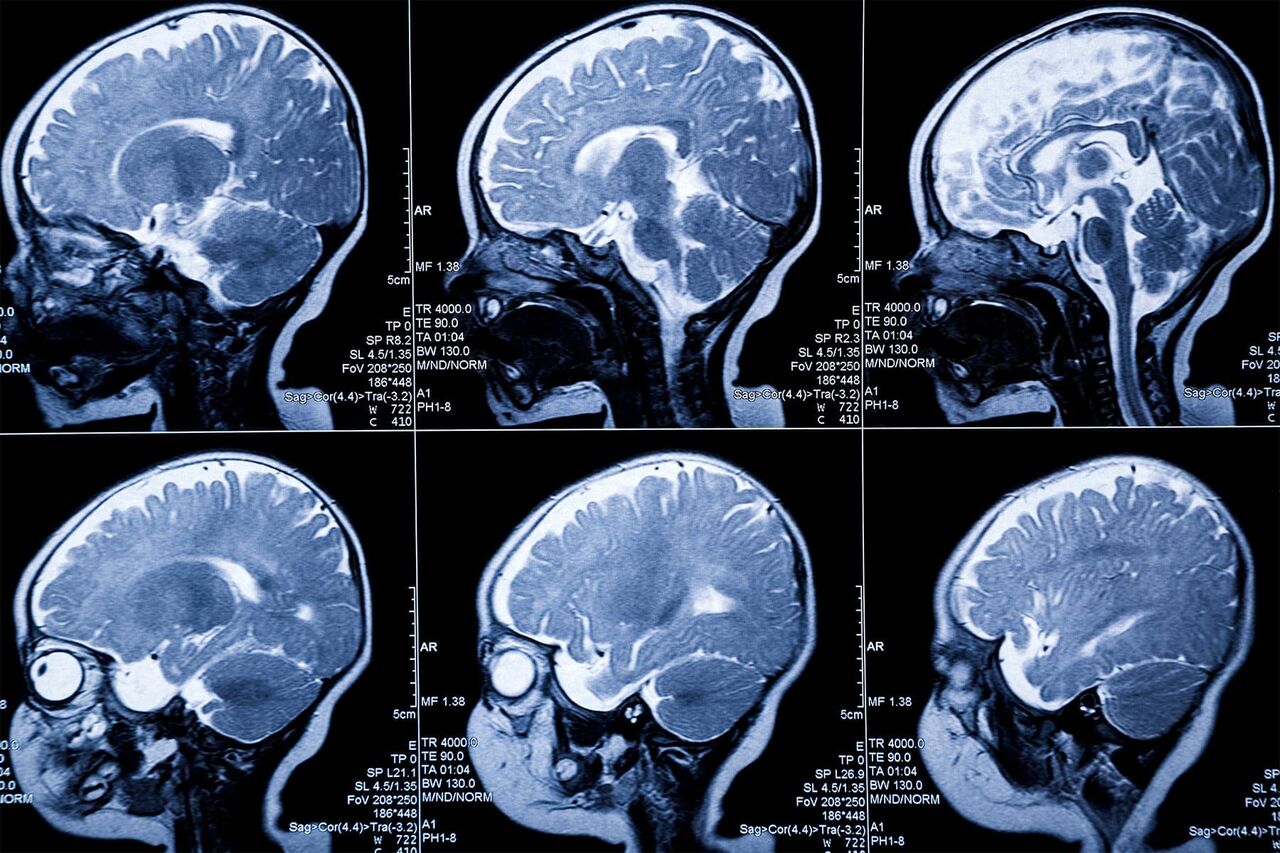

یک شرکت استرالیایی با همکاری گروهی تحقیقاتی در دانشگاه استرالیای جنوبی موفق به توسعه یک دستگاه تصویربرداری(MRI) نانویی شده که قابلیت تشخیص زودهنگام سرطان از جمله سرطانهای مغز و پروستات را دارد.

با همکاری شرکت استرالیایی فرونووا (Ferronova) که در حوزه تشخیص سرطان فعالیت دارد با پژوهشگران دانشگاه استرالیای جنوبی، یک فناوری جدید برای تصویربرداری دقیق از سرطانهای تهاجمی مغز طراحی شده است. این دستگاه نانویی میتواند به هزاران نفر که هر ساله با این بیماری کشنده تشخیص داده می شوند، کمک کند.

این دستگاه جدید تصویربرداری، یک MRI مبتنی بر فناورینانو بوده که نشانگر خاصی را هدف قرار میدهد؛ نشانگری که در بیش از ۹۰ درصد تومورهای جامد از جمله سرطانهای مغز با درجه بالا یافت میشود.